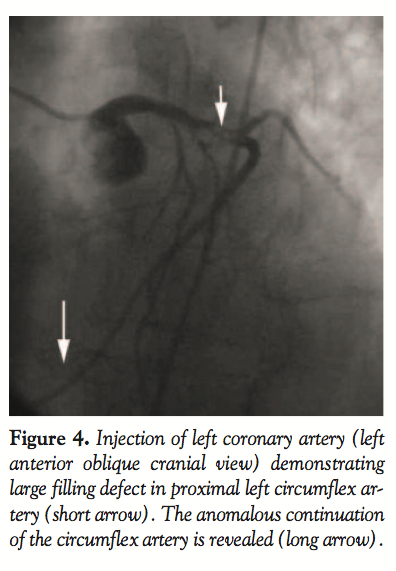

Nonselective injection in the right sinus of Valsalva during coronary angiography

revealed the right coronary artery (RCA) to be congenitally absent (Figure 3). A single coronary artery arose from the left coronary sinus. The left main coronary artery bifurcated into the left anterior descending (LAD) and left circumflex arteries. The LAD had mild proximal calcified stenosis of less than

50%. A 75% lesion in a small caliber first diagonal branch was noted. A critical (> 90%) narrowing in the proximal portion of the left circumflex artery (LCX) was present. This lesion demonstrated a large, hazy filling defect consistent with intracoronary thrombus. Angiographic cutoff of the posterior-lateral vessel suggested distal embolization of thrombus (Figures 4 and 5). The LCX continued along the atrioventricular groove, giving off posterior left ventricular and posterior descending (PDA) branches. The vessel then continued beyond the PDA, following the

course of the right atrioventricular groove in the typical distribution of the right coronary artery (RCA) and provided multiple right ventricular marginal branches.